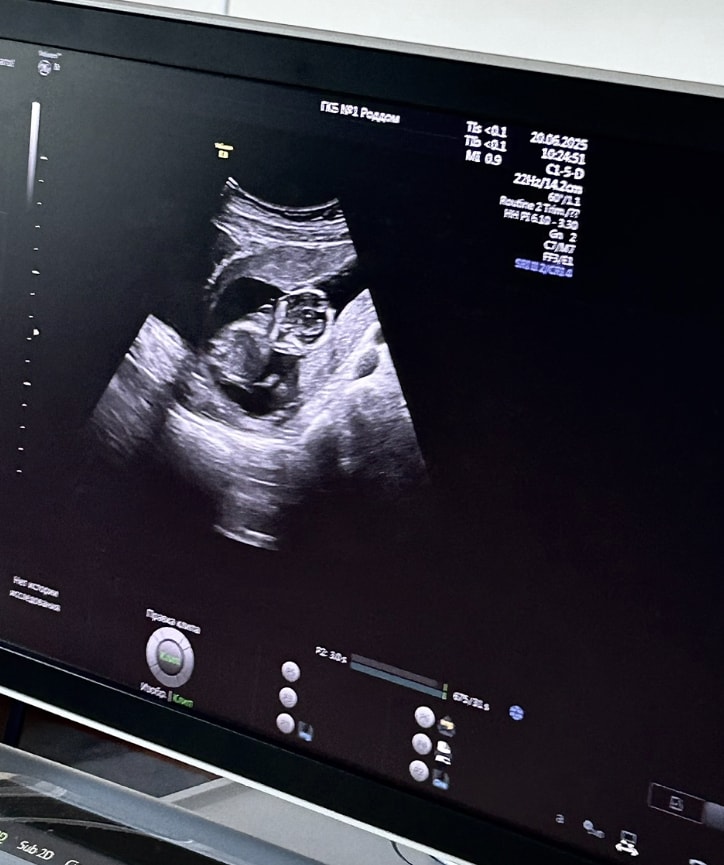

1 скрининг

Здравствуйте,сходила на 1 скрининг ,врач конечно был грубый ,посмотрел за 3 минуты и выгнал ,от волнения даже не успела ничего спросить ,по заключению все в порядке с малышом,только что то переживаю что тонус матки будто бы ,может кто то разбирается ,посмотрите пожалуйста